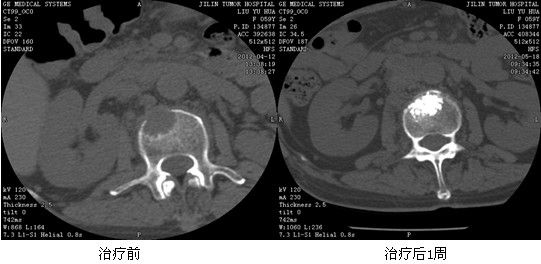

典型病例:赵XX,女,38岁,原发性肝右叶癌(BCLC C期)、多发性骨转移癌。左侧髋部及第4腰椎发现转移,左髋部疼痛明显,腰背部疼痛明显。给予125I放射性粒子植入及骨水泥局部填塞治疗后疼痛症状明显减轻,病灶明显萎缩。